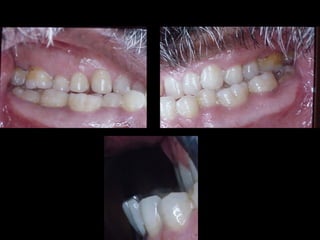

Valoración Clínica dela Paciente En términos generales podemos decir que la paciente tiene una cara armónica y aceptable, sin embargo observaciones métricas delatan: En términos generales podemos decir que la paciente tiene una cara armónica y aceptable, sin embargo observaciones métricas delatan: Laterognatia, manifestada por 3 grados de desviación del Mentón con respecto a la línea media real. Laterognatia, manifestada por 3 grados de desviación del Mentón con respecto a la línea media real. Hipoplasia moderada del maxilar del lado derechoHipoplasia moderada del maxilar del lado derecho Perfil cóncavoPerfil cóncavo Ligera incompatibilidad labialLigera incompatibilidad labial Depresión malarDepresión malar

La paciente muestrauna franca disgnatia, clínicamente observamos malposición dentaria secundaria a la falta de armonía máxilomandibular. La paciente muestra una franca disgnatia, clínicamente observamos malposición dentaria secundaria a la falta de armonía máxilomandibular.

Marcada Clase III HábitoLingual Marcada Clase III Hábito Lingual Sobremordida horizontal: –1.5 mm Sobremordida vertical: + 1 mm. Sobremordida horizontal: –1.5 mm Sobremordida vertical: + 1 mm.